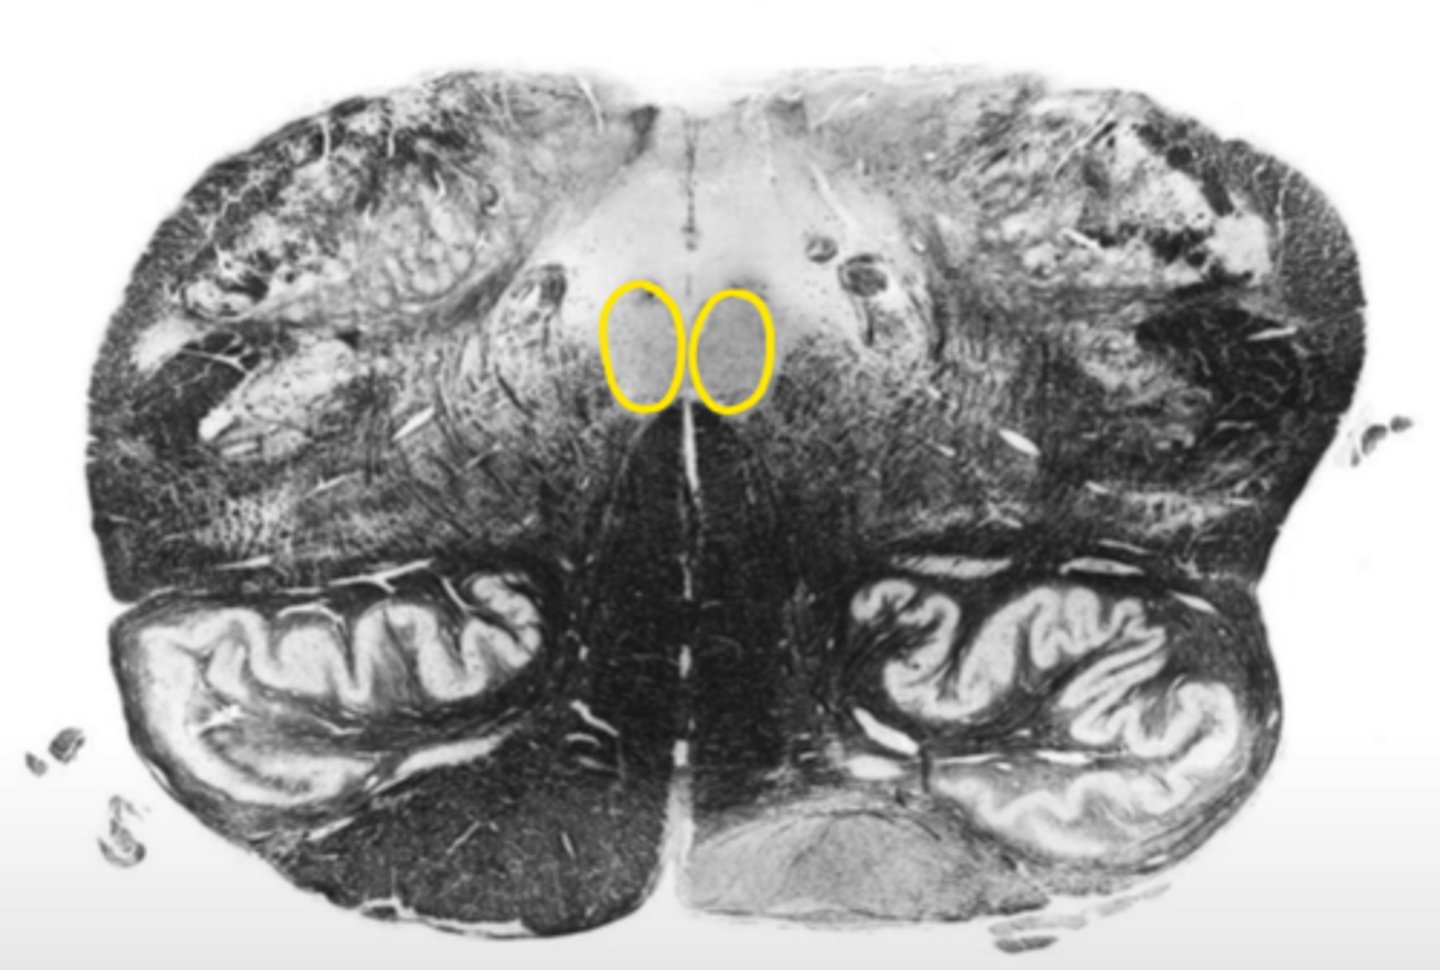

medial lemniscus

ID the structure